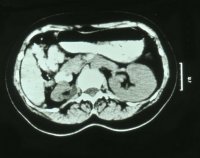

Neben der Anamnese, körperlicher Untersuchung, Messung des Blutdruckes sowie der Laboruntersuchungen: Urinstatus, Serumkreatinin und -Elektroylte ist die Sonographie zur Feststellung einer einseitig kleinen Niere zielführend (Abbildung 10a). Zur Diagnostik zählt fernerhin die NFZG (Abbildung 10b) bzw. Computertomographie.

Computertomographie zur Diagnostik der kleinen Niere. Zum Beispiel eine pyelonephritisch veränderte linke Niere im Computertomogramm und im weiteren Beispiel CT und Organpräparat einer rechtsseitigen kleinen Niere.

Und in einem weiteren Beispiel CT und Organpräparat einer rechtseitigen "kleinen Niere" (Abbildung 11, 12ab).